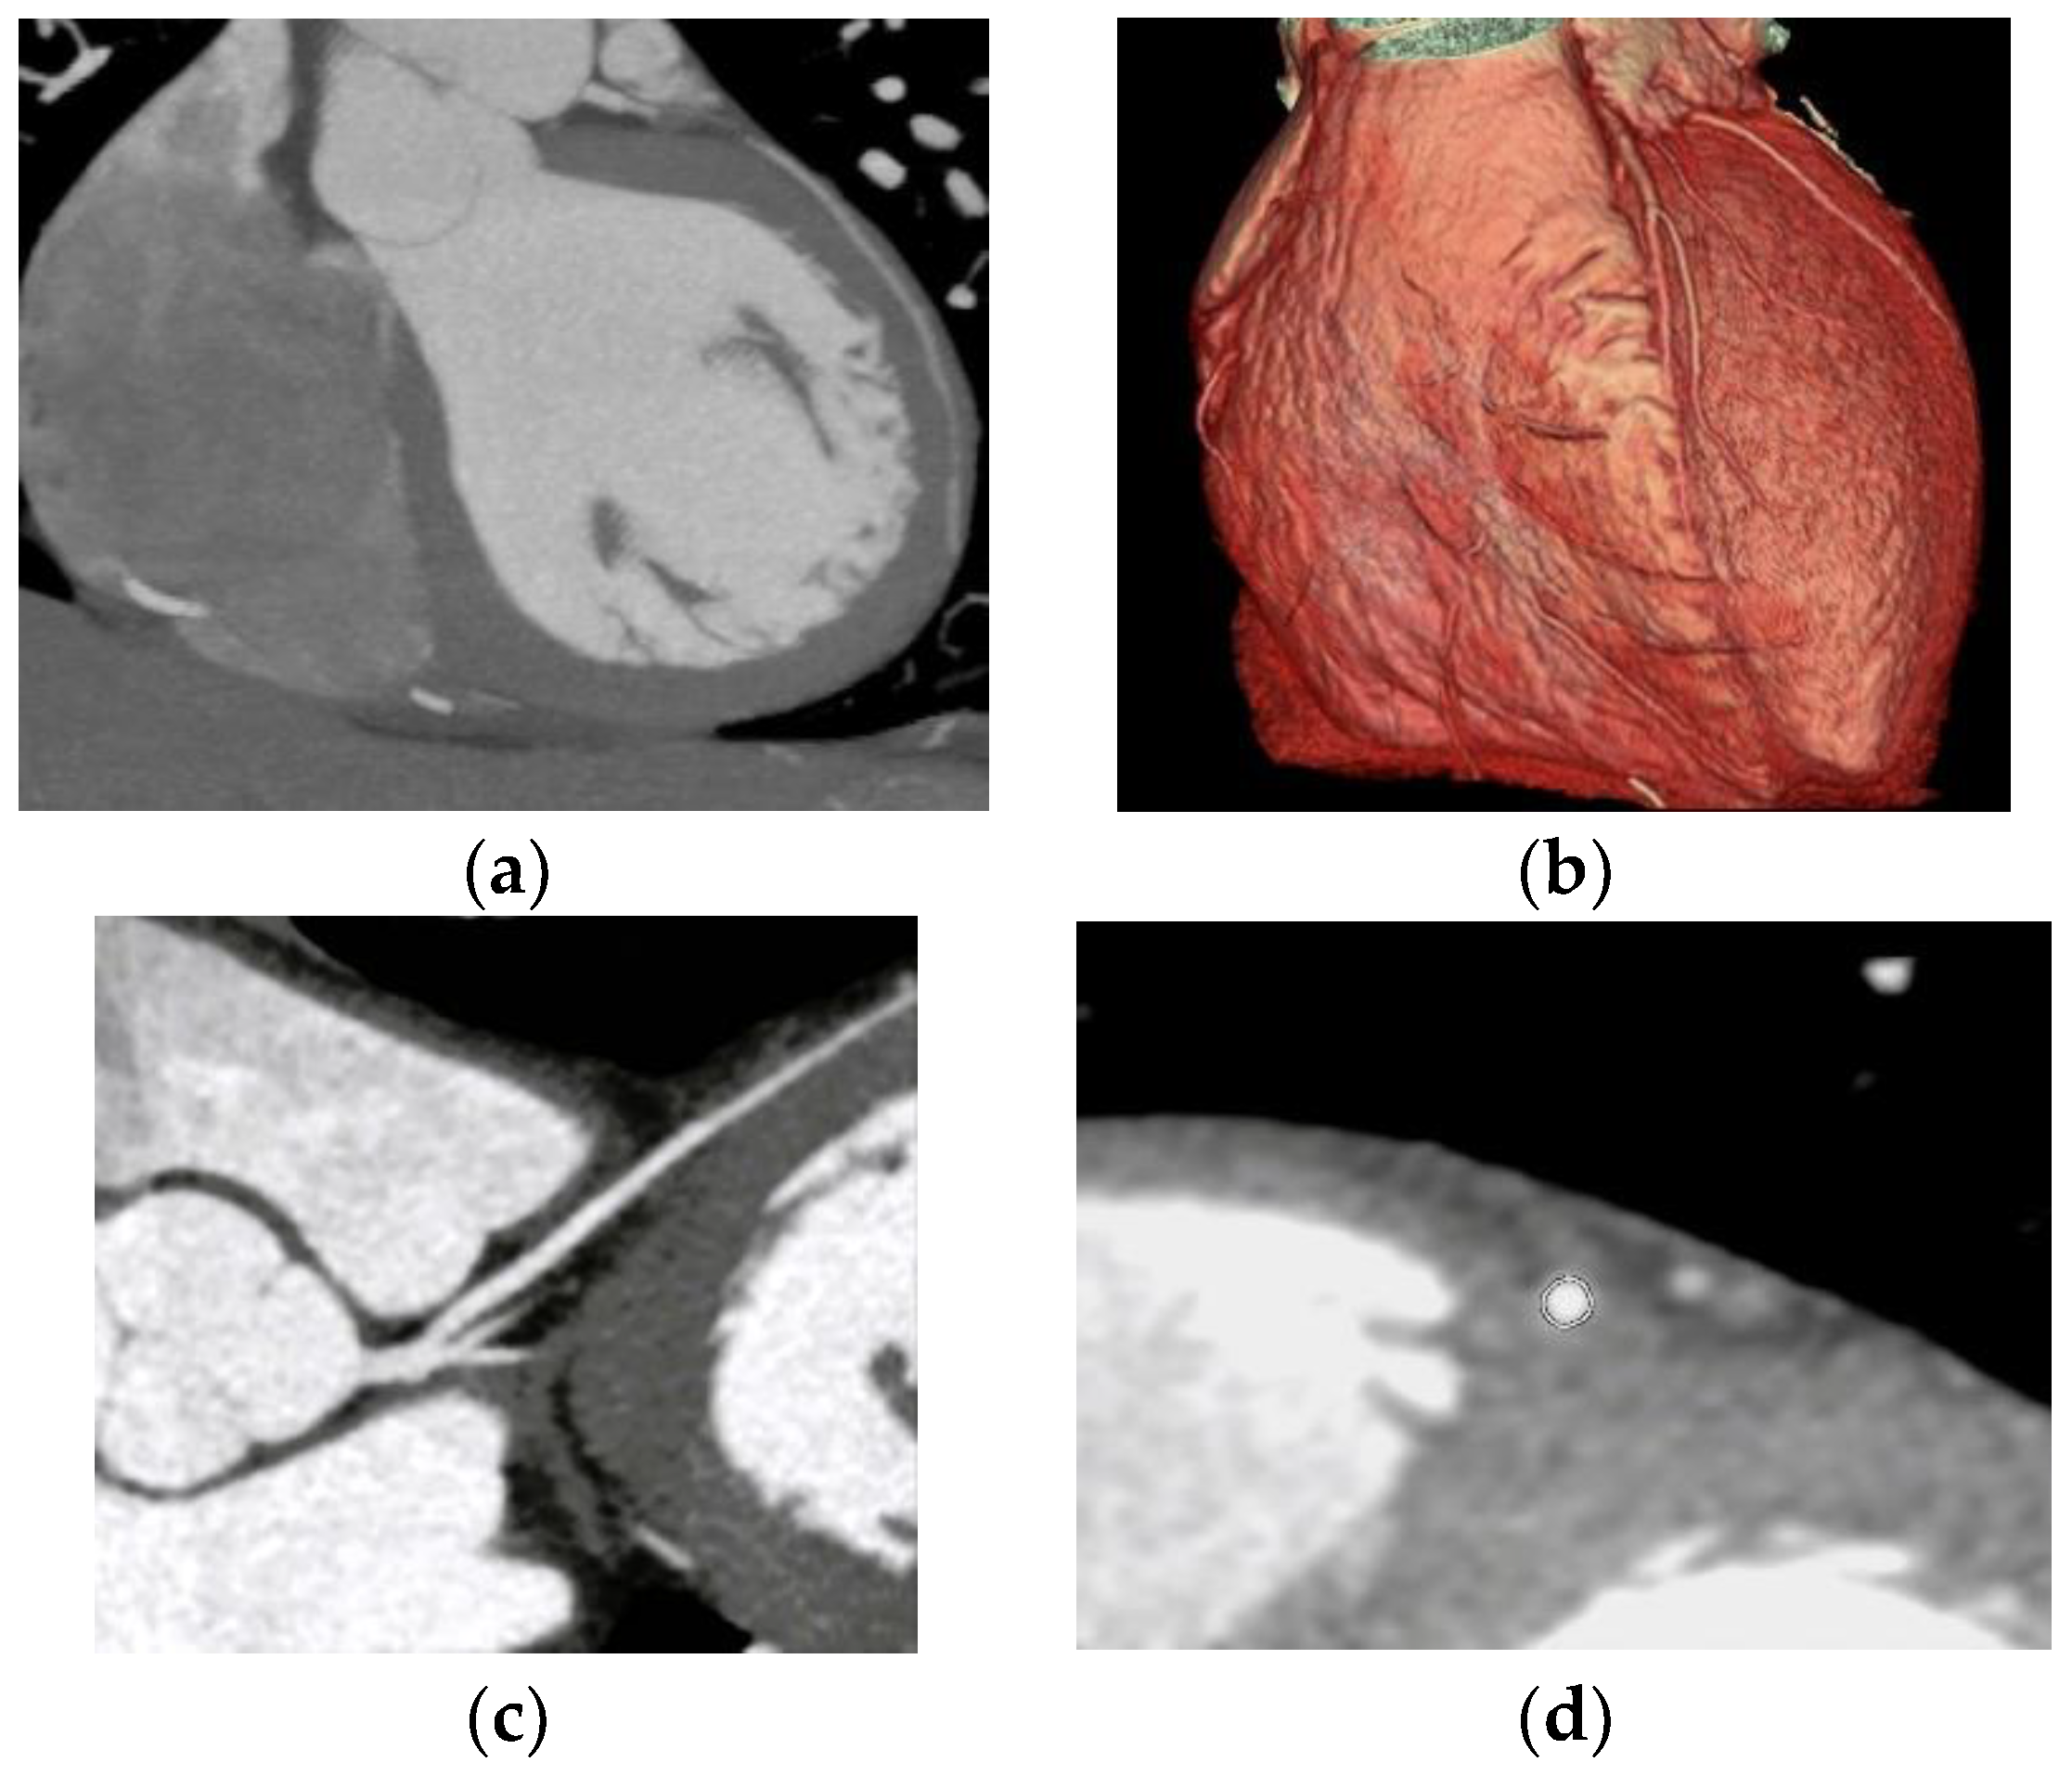

One case of right coronary anomaly originating from the left coronary sinus was found, with an anomalous course between the left pulmonary artery and the aorta, according to

Figure 2.

Two cases of separate origins of LAD and LCX arising directly from the left coronary sinus were found, as illustrated in

Figure 3.

One case of detachment of the left main coronary artery from the left coronary sinus at an acute angle was found (

Figure 4).

One case of congenital cardiac malformation with transposition of the great arteries and associated variation of origin and course of the coronary arteries was found (

Figure 5).

Nine cases of coronary anomalies with intramuscular bridging of the left anterior descending artery were found (

Figure 6).

One case of CAA with a right coronary anomaly originating from the left coronary sinus and an anomalous course between the pulmonary artery and the aorta was detected; a dynamic compressive effect could not be excluded at this level. According to the anatomical classification of the CAA of Angelini, there are several possible routes for the anomalous location of the coronary ostium at improper aortic sinus: in the posterior atrioventricular groove, retroaortic, between the aorta and the pulmonary artery, intraseptal, anterior to the pulmonary flow, in the posteroanterior interventricular groove [

8]. The CAA with a route between the aorta and the pulmonary artery is considered the highest-risk route and is associated with an increased risk of sudden death. Young people are the most vulnerable to sudden death; the risk decreases for middle-aged and elderly people [

5,

21,

22]. One hypothesis for why this effect occurs is that, during exercise, the aortic root and the pulmonary trunk expand and compress the coronary that passes between them. Another hypothesis is that the course of the coronary artery is partially embedded in the aortic wall and is laterally compressed during exertion [

5,

22,

23].

Two cases of separate origins of the LAD and LCX directly from the left coronary sinus were detected. Separate origins of LAD and LCX from the left coronary sinus is considered a benign variant, but some CAA classifications include it. It is considered a common CAA with a frequency between 0.41% and 0.67% [

5,

24].

One anomaly of detachment of the left main coronary artery from the left coronary sinus at an acute angle was encountered. In terms of route, the normal proximal orientation of the LM and RCA is 45° to 90° to the aortic wall, with a subepicardial extramural route to destination [

5]. In scientific literature, the prevalence of acute angles of detachment of the coronary artery from the coronary sinus is 2% [

2].

Coronary anomalies may coexist with other cardiac anomalies [

1]. For instance, in 26% of cases, coronary anomalies are associated with aortic root anomalies [

5]. In this study, one congenital cardiac malformation with corrected transposition of the great arteries was encountered. The CCTA has an increased capacity to diagnose cardiac malformations, coronary anatomy, and their relationship. In patients with transposition of the great vessels, the identification of coronary anatomy is fundamental for patient management and, eventually, for surgical intervention [

25,

26]. The cardiac malformation in this study is on the benign spectrum of the condition due to the presence of three separate sinuses and no malignant coronary course running between the aortic pathway and the right ventricular outflow tract.

In coronary intramyocardial bridging, a portion of the epicardial coronary pathway is covered by heart muscle; the artery most affected by this condition is the LAD artery [

1]. Nine cases of coronary artery intramuscular bridging were detected, and the findings are consistent with the scientific literature; all cases included the left anterior descending artery. Intramuscular bridges are frequently an incidental encounter in CCTA examinations, and only some of them associate systolic compression with a possible reduction in myocardial perfusion. Intramuscular bridges are sometimes associated with atypical angina pectoris. The impact of myocardial bridges on the risk of myocardial infarction is debatable. They are generally considered benign conditions, but the length and depth of the intramyocardial bridge may influence the degree of coronary dysfunction, with some studies showing an association of myocardial bridges with increased risk of myocardial infarction [

27,

28,

29].